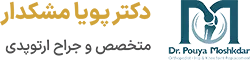

جراحی تعویض مفصل زانو چیست؟

عمل تعویض مفصل زانو (Knee replacement) یک جراحی ارتوپدی پیشرفته است که در آن بخش های آسیب دیده یا فرسوده مفصل زانو با قطعات مصنوعی جایگزین میشوند. این عمل برای بیمارانی انجام میشود که دچار آرتروز شدید، آسیب دیدگی یا بیماری های مفصلی هستند و درد یا محدودیت حرکتی آن ها با روشهای غیرجراحی مانند تزریق ژل هیالورونیک اسید به زانو بهبود نیافته است. مفصل مصنوعی، عملکرد طبیعی زانو را بازمیگرداند و فعالیت های راه رفتن و نشستن و … را بهبود میبخشد.

مراحل جراحی تعویض مفصل زانو

پس از ورود به اتاق عمل، بیمار تحت بیهوشی قرار میگیرد و زانو با مواد ضدعفونی تمیز میشود. آنتیبیوتیک پیشگیرانه نیز تزریق میشود. بهترین جراح تعویض مفصل زانو با ایجاد یک برش در جلوی زانو، به مفصل دسترسی پیدا کرده و بافتهای نرم و عضلات را کنار میزند.

غضروف و استخوانهای آسیبدیده برداشته شده و سطح استخوانها با دقت شکلدهی میشود تا پروتز بهخوبی جایگذاری شود. پروتز شامل قطعات فلزی برای استخوان و قطعه پلاستیکی برای ایجاد سطح لغزنده است که بهطور محکم در جای خود نصب میشود.